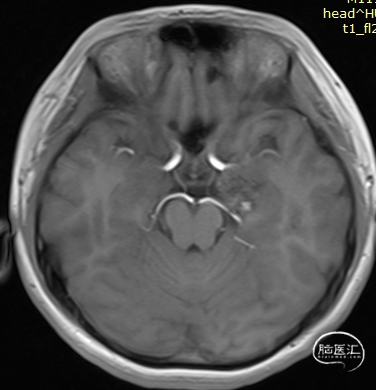

术前影像:

左侧海马旁回海绵状血管瘤。